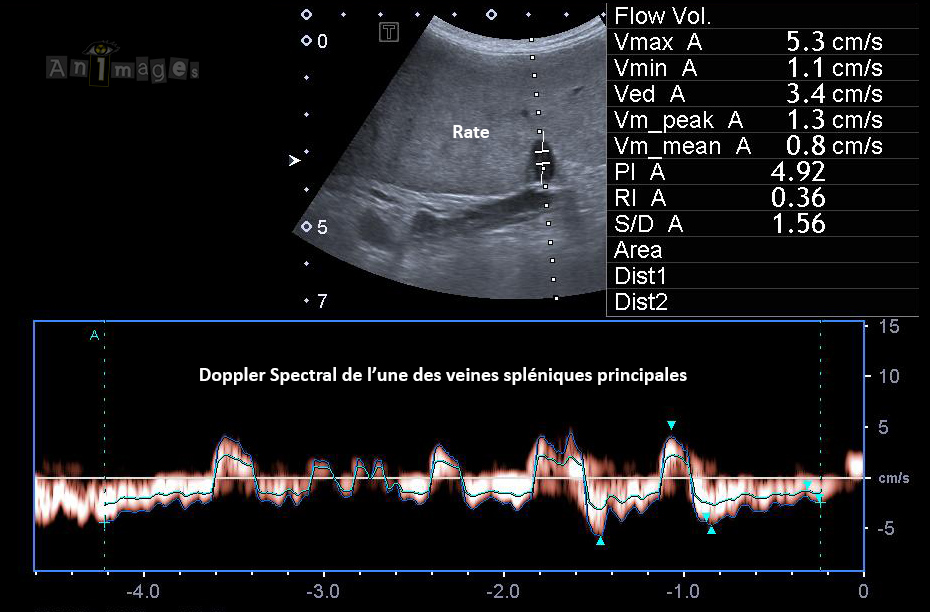

Doppler Spectral